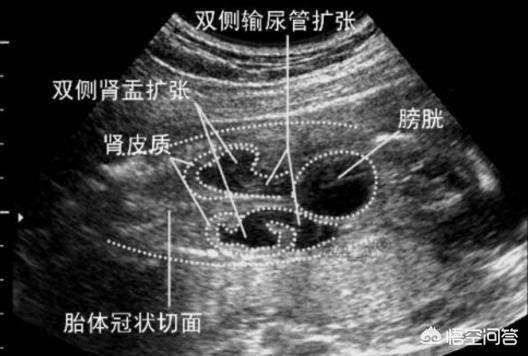

但话又说回来了,相对异常也是异常,也会增加新生儿的异常。就拿肾积水来说吧,超过0.6cm就算超出了正常范围,一般认为超过2cm以上才有可能造成一定的肾脏损伤。

胎儿的肾脏会有轻度的分离,6毫米以下,如果胎儿的肾积水不超过10毫米,那么是正常的范围。

然而,如果胎儿的孕周在30周后,胎儿的肾小盏在不断增大,或者是胎儿的肾盂分离还是大于或等于10毫米,那么医生会确诊胎儿患上了肾积水。

从数值上来看,胎儿肾积水1.9厘米超出正常数值的范围,胎儿的情况比较严重。

如果B超显示胎儿双侧重度肾积水,肾脏比较差,或者是输尿管畸形,那么医生不建议孕妇妊娠。